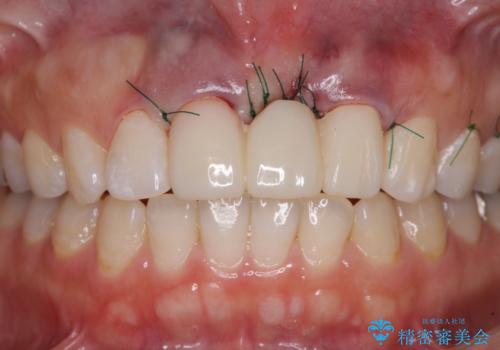

欠損部の歯肉が窪んでいるため、歯肉移植により形態を改善し、オールセラミックブリッジにて補綴することとしました。

セラミック治療の注意事項(リスク・副作用など)

- 天然歯を削ります

- 硬い素材は天然歯を傷つけてしまう場合があります

- かみ合わせや歯ぎしりが強すぎる方はセラミックが割れてしまう可能性があります